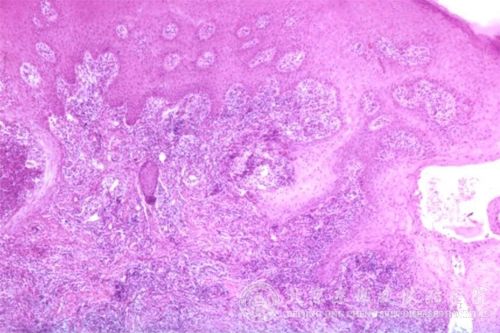

怎么根据病因治疗皮肤病?现在是各种皮肤病的高发季节,我们身边有很多人被各种皮肤病所困扰,因此很多人会问这个各种皮肤病问题。但目前有很多患者对各种皮肤病了解不足,错过了较佳各种皮肤病治疗时机,从而导致各种皮肤病病情发展严重,增加了各种皮肤病患者痛苦,同时也增加了各种皮肤病治疗难度。及时发现各种皮肤病,及时治疗各种皮肤病,才可以减少各种皮肤病皮肤损伤。知道怎么根据病因治疗皮肤病,就可以及时及时治疗各种皮肤病。

北京京城皮肤医院指出,根据各种皮肤病发病的原因选择药物。如对脓疱疮、等细菌感染性皮肤病,应选用抗菌药物。对于、花斑癣等真菌感染性皮肤病,应选择抗真菌药物。

对于单纯疱疹等病毒感染的皮肤病则应选用药物。而对于、神经性皮炎等非感染性皮肤炎症,可适当选用皮质类固醇激素治疗。